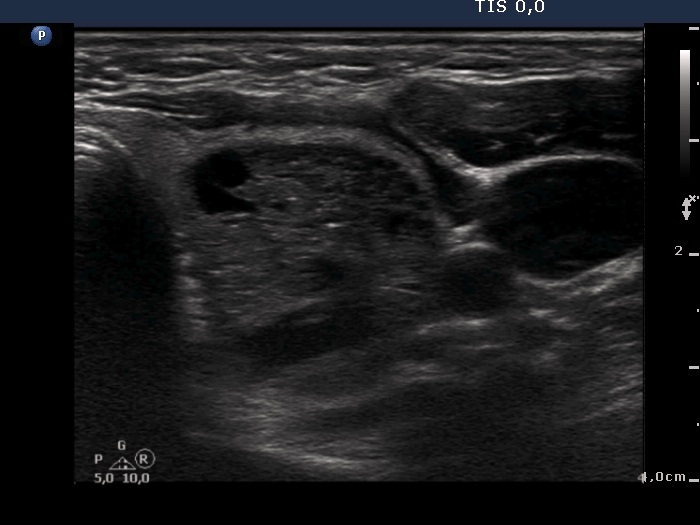

100 consecutive patients with thyroid nodule - Case 24. (ultrasonographic picture 8)

Left lobe, horizontal scan. Theupper part of the nodule contains a moderately hypoechogenic solid part presenting numerous hyperechogenic figures.